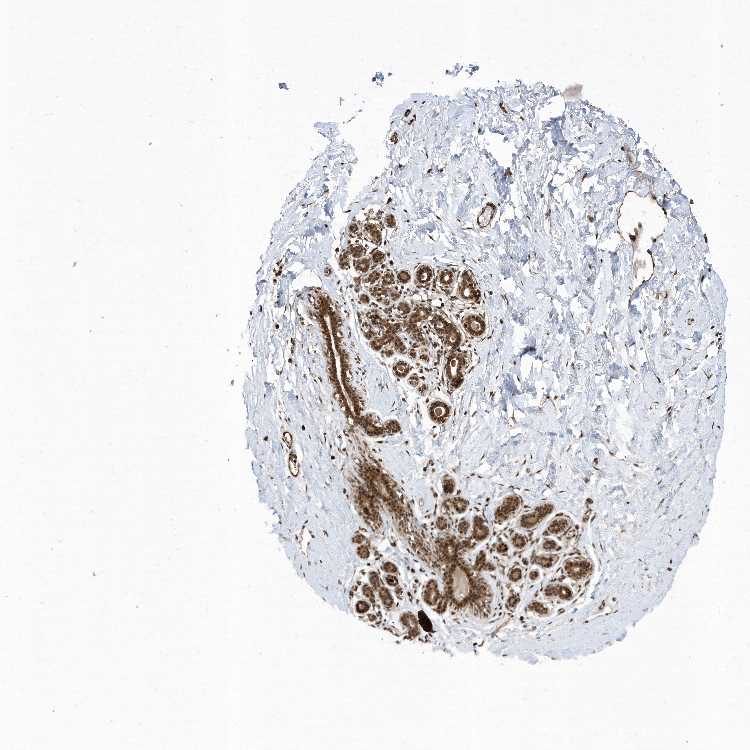

BREAST - Antibody stainingi

Antibody staining in the annotated cell types in the current human tissue is reported as not detected, low, medium, or high, based on conventional immunohistochemistry profiling in selected tissues. This score is based on the combination of the staining intensity and fraction of stained cells.

Each image is clickable and will lead to virtual microscopy that enables deeper exploration of all samples and also displays staining intensity scores, fraction scores and subcellular localization as well as patient and tissue information for each sample.

Antibody HPA035772

Adipocytes Medium

Glandular cells High

Myoepithelial cells High